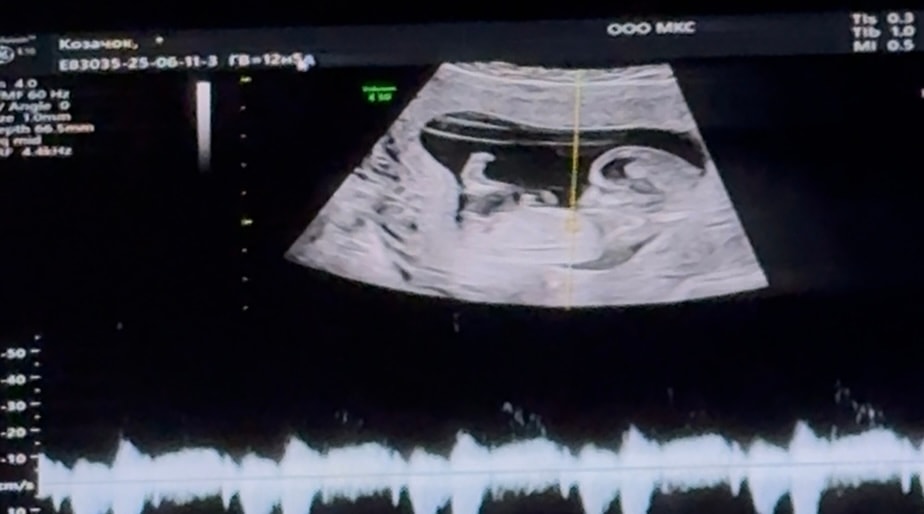

Определение пола по половому бугорку.

Нужен совет (вне обсуждений основной темы сообщества, но в рамках разумного)Всем привет! На первом скрининге сказали 95% девочка, а сегодня была на УЗИ перед отпуском, сказали, что больше похоже на мальчика 😆 Кто умеет определять по половому бугорку?